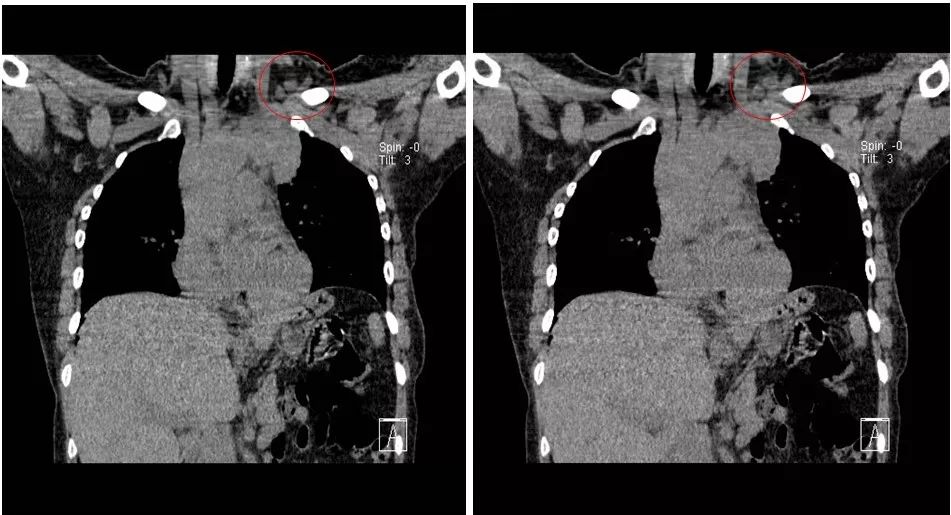

接受TC(卡铂)+曲妥珠单抗单周方案治疗。治疗2个周期后复查:淋巴结彩超示:左锁骨上淋巴结缩小,大的0.6×0.4cm;复查胸部CT示:左侧纵隔肿物缩小,最大截面约6.0×2.9cm。治疗4个周期后再次复查,淋巴结彩超示:左锁骨上淋巴结缩小,大的0.6×0.4cm;复查胸部CT示:左侧纵隔肿物缩小,最大截面约3.1×2.4cm。治疗6个周期后再次复查,淋巴结彩超示:左锁骨上淋巴结缩小,大的0.3×0.3cm;复查胸部CT示:纵膈肿物缩小明显,病灶局部包绕头臂静脉,与胸壁边界不清。评价治疗有效,继续行TC(卡铂)方案化疗+靶向治疗。治疗8周期后再次胸部CT示:纵隔肿瘤缩小明显,最大截面由最初的7.2×2.9cm缩小为2.7×2.9cm,评价为PR。8周期治疗后,患者出现腹泻,大便次数8-10次/天,水样便,影响日常生活,根据NCI分级属3级重度腹泻。10天左右缓解;II度骨髓抑制。患者拒绝继续化疗,曲妥珠单抗改为21天/周期。

图5. 治疗8周期后复查胸部CT平扫